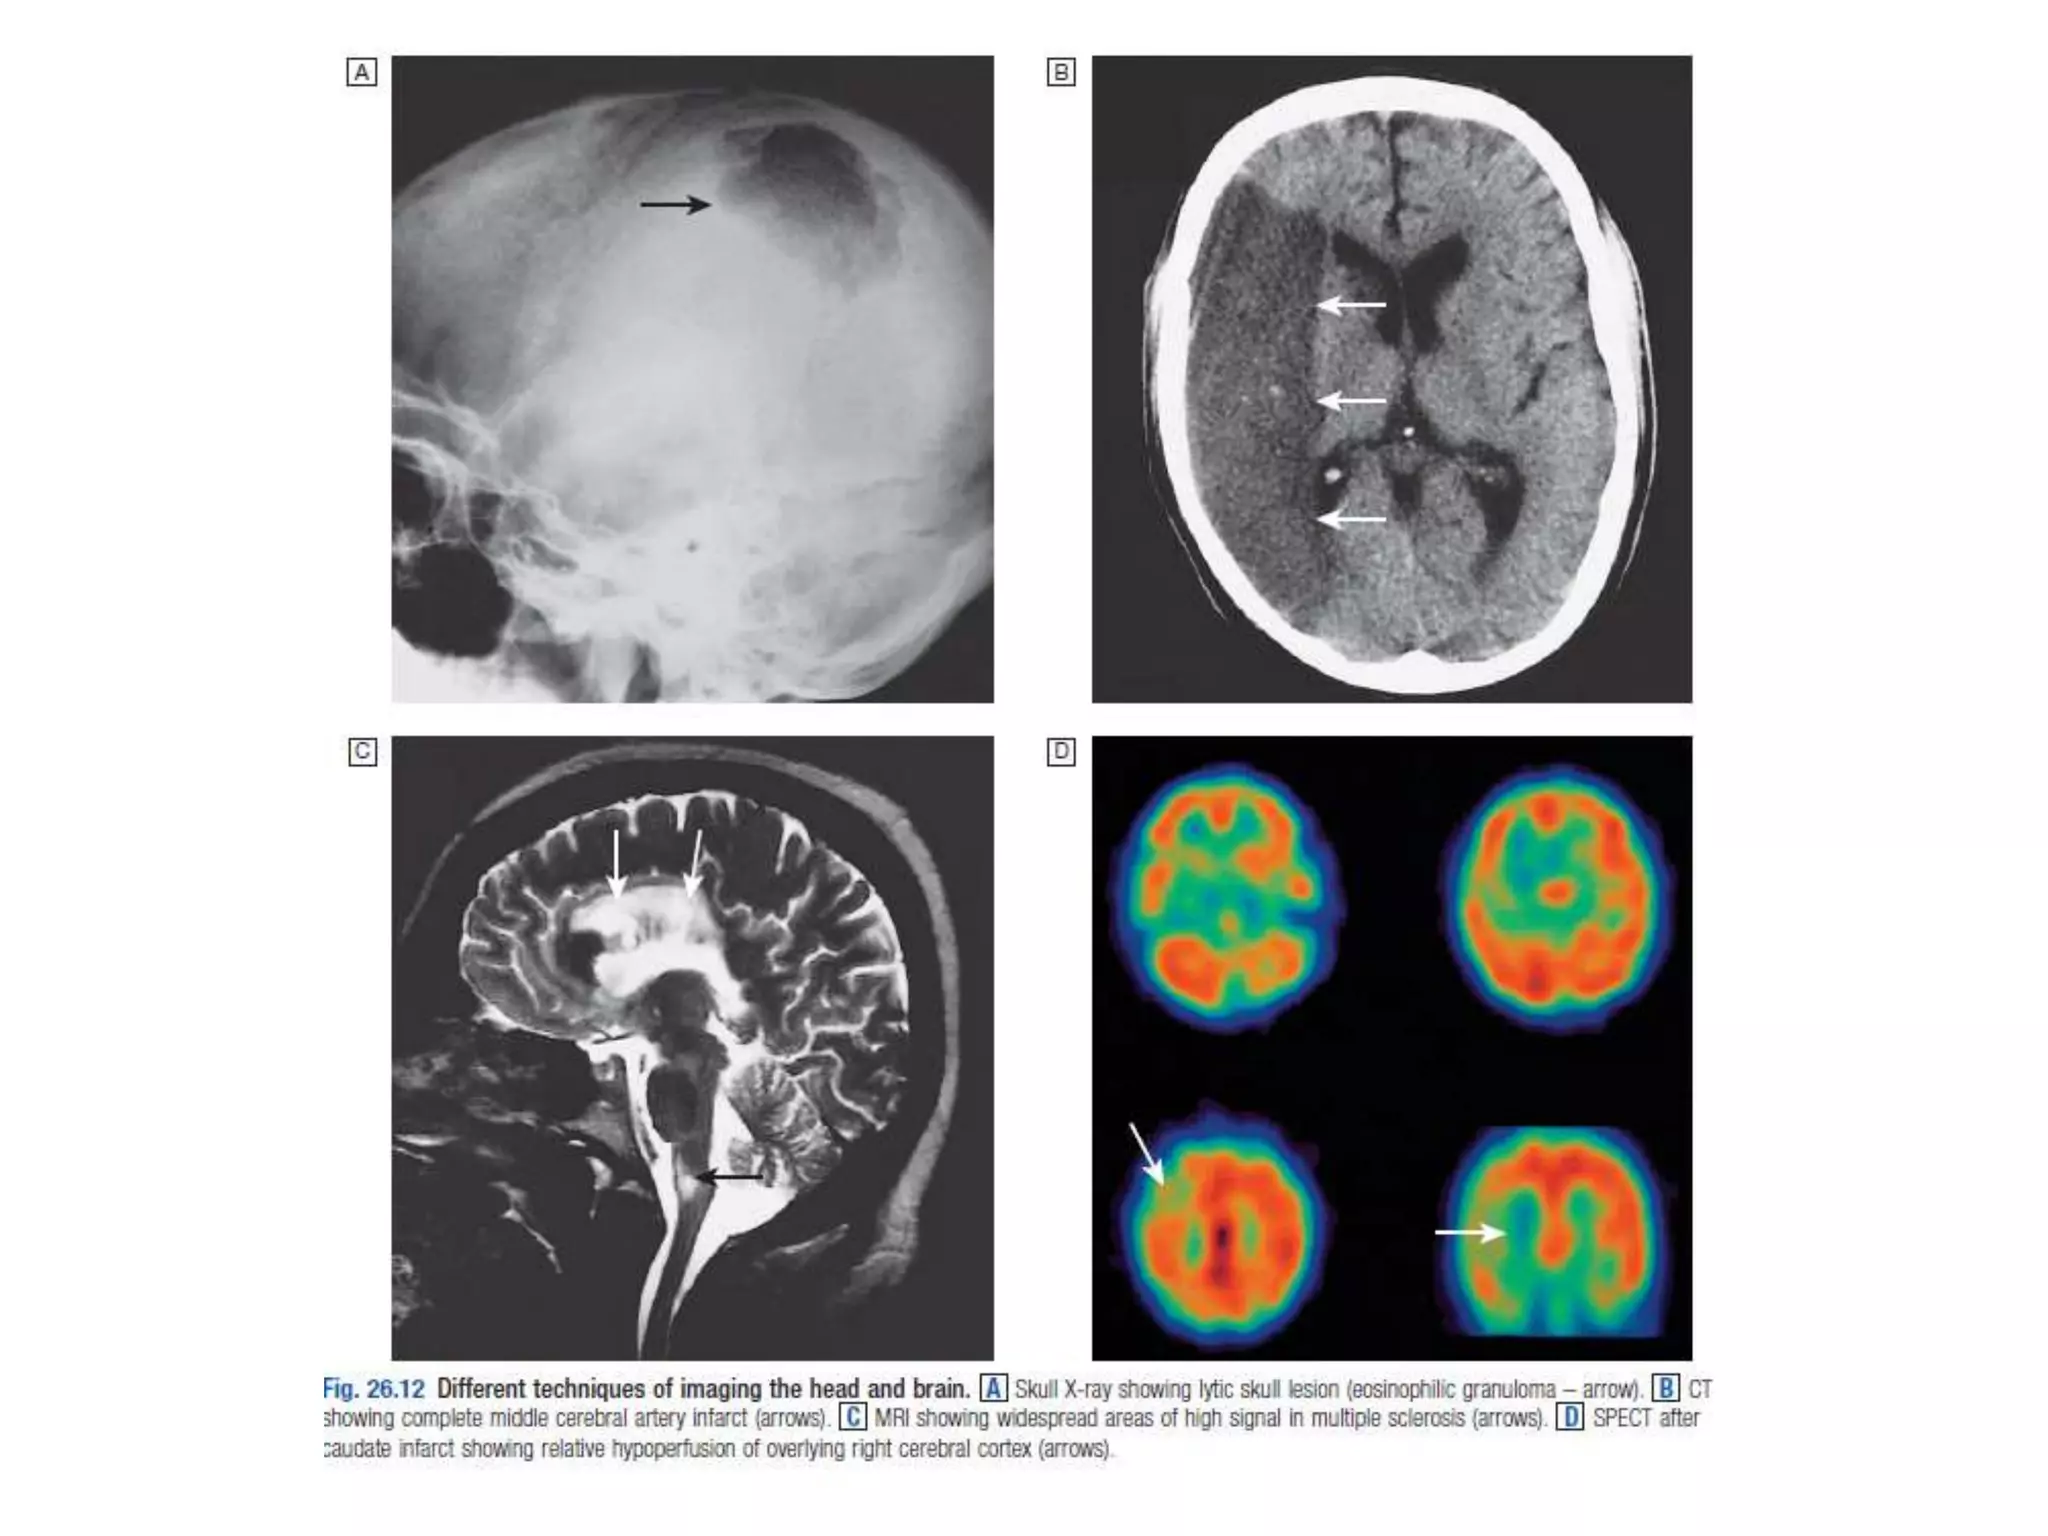

Figure 11.32 Left atrial dilatation.

This is a penetrated PA chest X-ray in a patient with mitral stenosis.

The dilated left atrium causes a bulge on the left heart border below

the pulmonary artery which is also dilated, widening of the carina

and the double density sign at the right heart border.

Figure 11.31 Pericardial effusion with tamponade:

There is a left hilar mass caused by carcinoma. Pericardial infiltration has

produced effusion and tamponade, evidenced by the severely enlarged

and globular cardiac silhouette. Malignant disease is now the most

common cause of tamponade in most developed countries.

Figure 11.35 Chest X-ray in acute left ventricular failure:

the patient had severe pulmonary oedema caused by acute

myocardial infarction. The heart is not yet enlarged, but there

is prominent alveolar pulmonary oedema in a perihilar (‘bat’s-

wing’) distribution. Note the bilateral pleural effusions.

Figure 11.32 Leftatrial dilatation. This is a penetrated PA chest X-ray in a patient with mitral stenosis. The dilated left atrium causes a bulge on the left heart border below the pulmonary artery which is also dilated, widening of the carina and the double density sign at the right heart border.

Figure 11.31 Pericardialeffusion with tamponade: There is a left hilar mass caused by carcinoma. Pericardial infiltration has produced effusion and tamponade, evidenced by the severely enlarged and globular cardiac silhouette. Malignant disease is now the most common cause of tamponade in most developed countries.

Figure 11.35 ChestX-ray in acute left ventricular failure: the patient had severe pulmonary oedema caused by acute myocardial infarction. The heart is not yet enlarged, but there is prominent alveolar pulmonary oedema in a perihilar (‘bat’s- wing’) distribution. Note the bilateral pleural effusions.